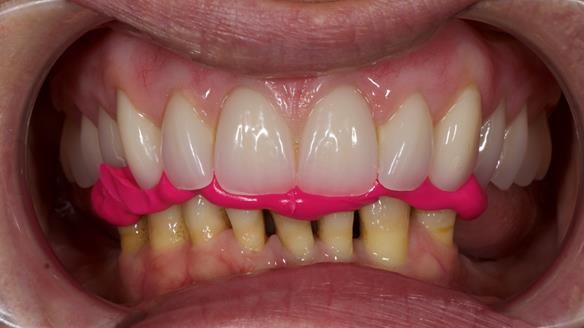

She had previously suffered from generalised periodontitis – stage IV, grade C, currently stable, with reduced attachment across the upper arch.

By the time she came to me, her periodontal condition was stable — but the aesthetics in the upper jaw were very poor.

We provided her with an immediate upper denture (Mk 1), followed by a definitive metal-based upper denture (Mk 2). A lower removable partial denture was discussed, to be made only if needed once the upper treatment was complete. However, at review, this wasn’t necessary — Adnana had excellent neuromuscular control and function, even with a shortened dental arch (SDA).

- Definitive denture (Mk 2), metal-based and custom-designed for her face

- A restored smile, restored lip support, and a patient who owned the journey